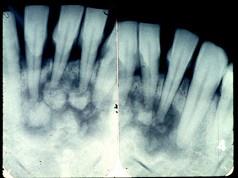

图为牙骨质瘤的X 线表现,关于此病描述不正确的是 ( )

A牙髓活力测试是阴性的

B来源于牙胚的牙囊或牙周膜

CX 线显示根尖周围有不透光的阴影

D生长缓慢,一般无自觉症状

E肿瘤紧贴牙根部,可单发或多发